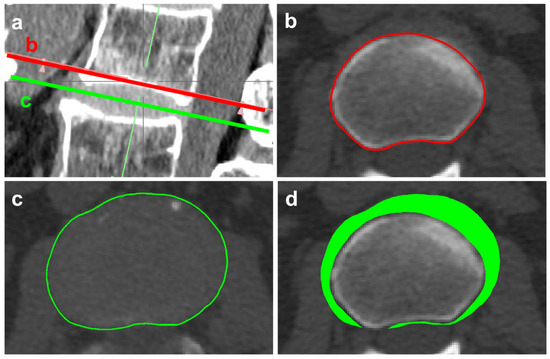

2.2. Computed Tomography Evaluation